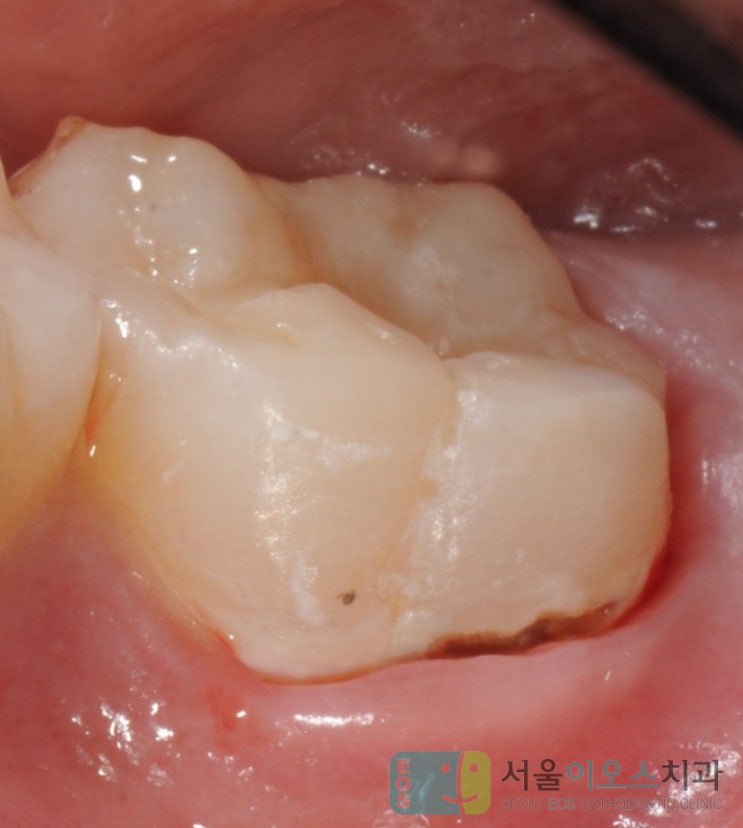

어금니 충치치료 안 하면 안 되나요?? 충치 단계와 검진 필요 이유

어금니 충치치료 안 하면 안 되나요?? 충치 단계와 검진 필요 이유 반갑습니다. 교정전문 서울이오스 소재...